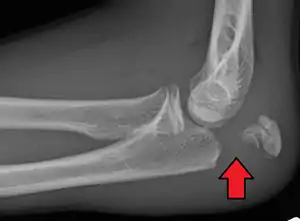

Olecranon fracture

Olecranon fracture is a fracture of the bony portion of the elbow. The injury is fairly common and often occurs following a fall or direct trauma to the elbow. The olecranon is the proximal extremity of the ulna which is articulated with the humerus bone and constitutes a part of the elbow articulation. Its location makes it vulnerable to direct trauma.

To assess an olecranon fracture, a careful skin exam is performed to ensure there is no open fracture. Then a complete neurological exam of the upper limb should be documented.[5][2] Frontal and lateral X-ray views of the elbow are typically done to investigate the possibility of an olecranon fracture.[1] A true lateral x-ray is essential to determine the fracture pattern, degree of displacement, comminution, and the degree of articular involvement.